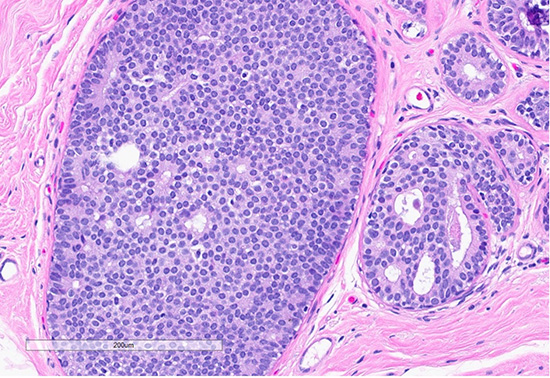

Figure 4: H&E section (top) shows a focus of usual ductal hyperplasia (UDH), characterized by expanded ducts filled with mildly polymorphous epithelial cells arranged in a haphazard pattern with irregular spaces. Scattered foci (bottom) exhibit features of columnar cell change, with the dilated ducts lined by columnar cells arranged perpendicularly to the basement membrane, with apical snouts.

Histological examination revealed lobules containing cells arranged in a cribriform pattern with eosinophilic to basophilic, round to oval, collagen-rich spherules (in this case mucinous spherules - may be called mucinous spherperolosis instead). Adjacent regions demonstrated a monomorphic proliferation of mildly atypical cells with round nuclei, indistinct nucleoli, and dyshesive features, along with intracytoplasmic lumina. Other foci were composed of ducts with monomorphic cells displaying ovoid to rounded nuclei in a solid and cribriform pattern, each focus measuring less than 2 mm. A focal area displayed ducts filled with polymorphous cells with peripheral elongated clefts. Additional ducts exhibited an architecturally “flat” pattern without cytologic atypia. The epithelial lining cells were predominantly columnar, with elongated nuclei oriented perpendicular to the basement membrane.